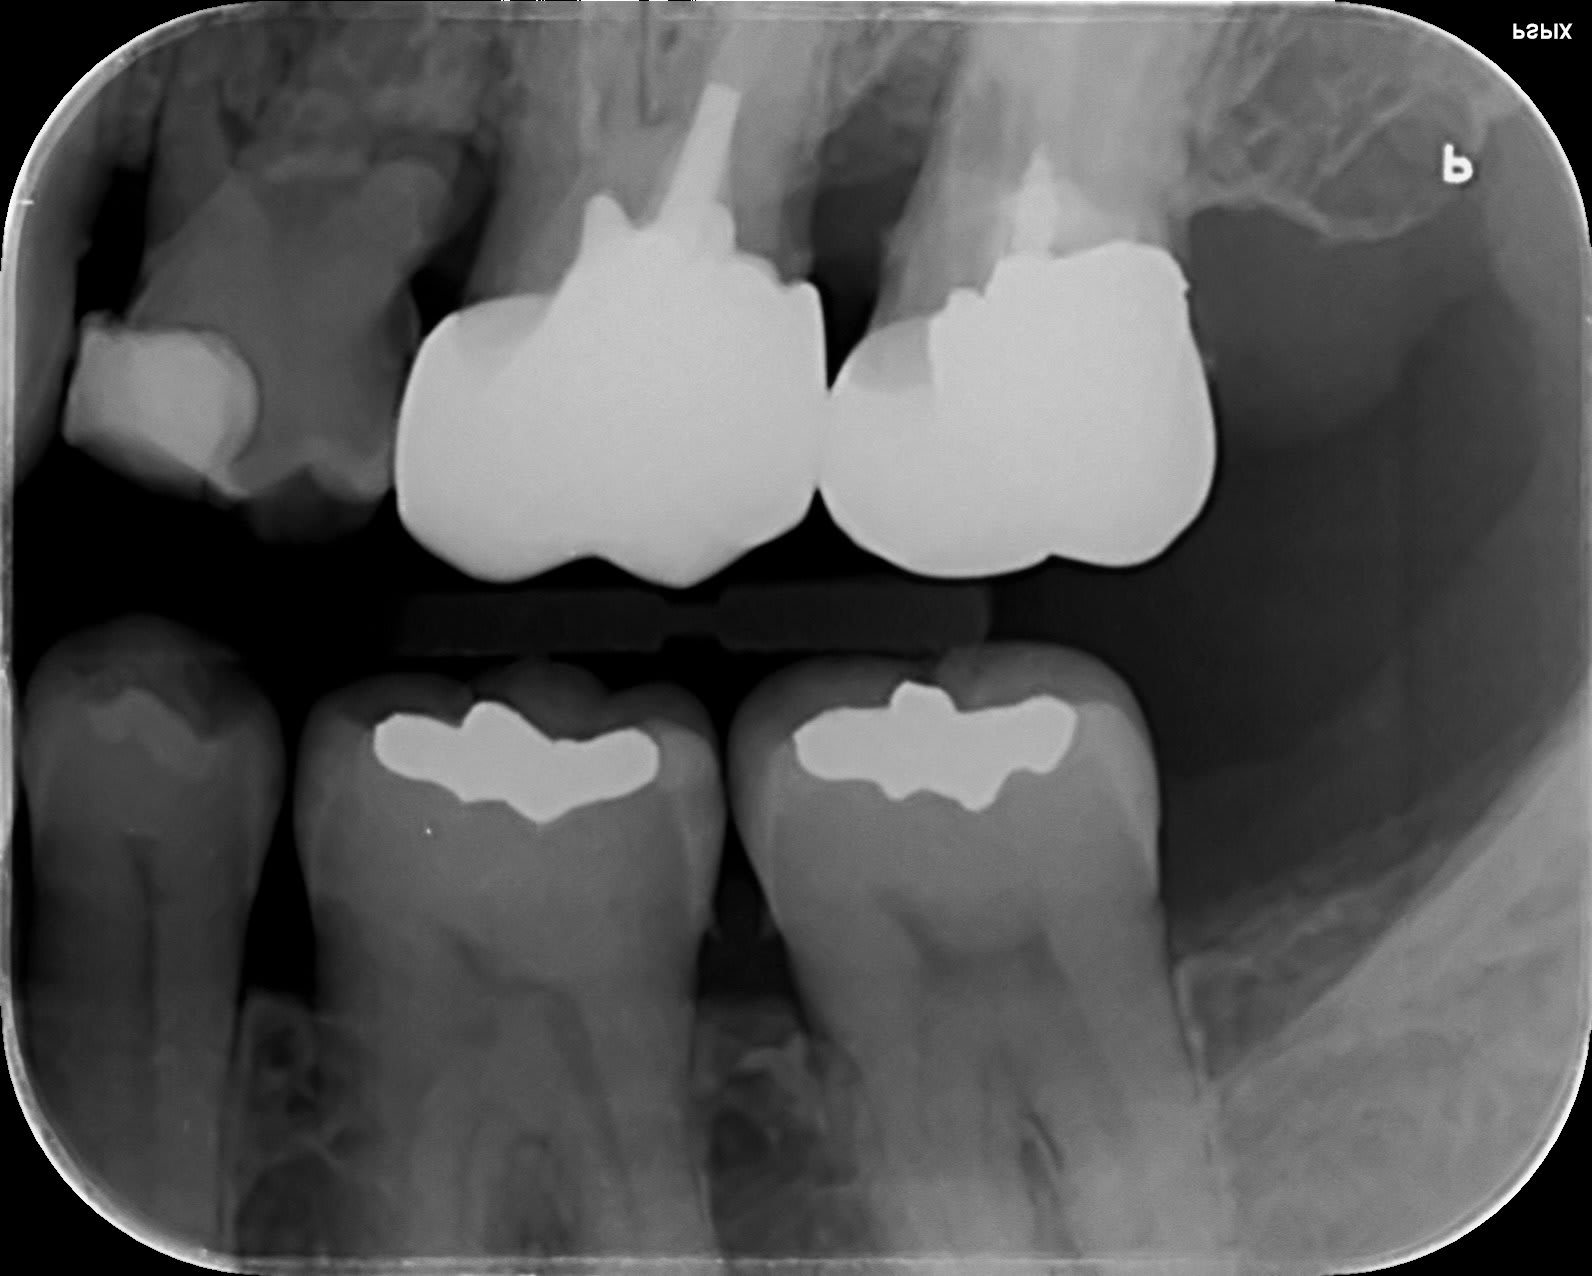

Patiente 54 ans, pas d’antécédent médical. Tabagisme 1 cigarette /jour.

Motif C: Douleurs types décharges électrique dans la tempe gauche, irradiante dans la mâchoire. Cédant régulièrement par tt antibiotiques au bout de 48 heures.

Crises récurrentes et de plus en plus rapprochées. A vu sont MG, otite écartée.

Diagnostic?

La paro entre 6 et 7 ?

Du du bimetalisme entre haut et bas.... Nan pas de cedation aux atb

La 5 de lait (?) qui est a moitié rongée au niveau des racines ?

On exclu la 65.

Paro, tu as une seule atteinte entre 26 27. Le reste est bien, donc c'est pas une parodontite généralisée. L'atteinte angulaire a un sens...

À mon avis t'es pas loin avec le bimetalisme.

La réponse est sur les radios pour une fois.

Toute la racine de 27 est bouffée !

La perte osseuse est la conséquence du truc et pas la cause.

On a l’impression d’une rhizalyse périphérique.

Corrosion, fêlure, sur occlusion, scew post...

Résorption interne, elle est en mesial de la pointe du screw-post. On la voit sur les Rx, surtout la retro-alveolaire et elle debouche au niveau de la lesion paro.

C’est une résorption cervicale externe et non interne :) Celle-ci tu l’as pas vu venir :)) on fait moins le malin tout d’un coup :)))

Bin non. Elle debouche pleine poche, tu vois sur la retroalveolaire la perfo qui va de dedans vers dehors.

Tiens regarde résorption cervicale externe :

Ça ressemble à ça non ?:)